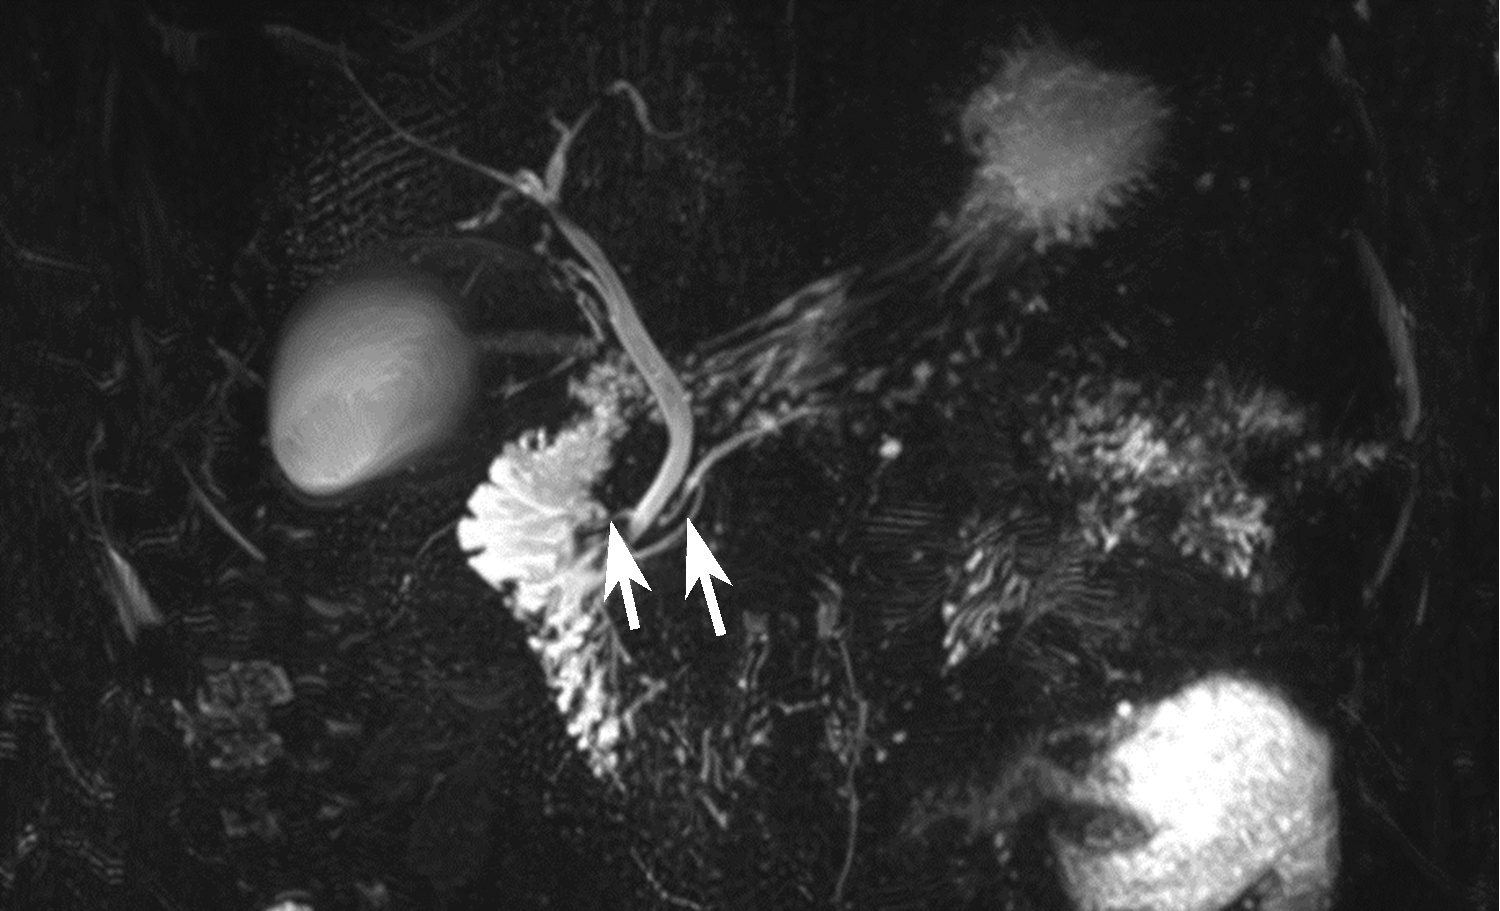

A case of idiopathic hypereosinophilic syndrome presenting with progressive multiple vascular lesions

Qingfang XIONG, Hao REN, Hui ZHOU, Xiaoning FENG, Duxian LIU, Yandan ZHONG, Yongfeng YANG

2022, 38(11): 2575-2577. DOI: 10.3969/j.issn.1001-5256.2022.11.027

Abstract(776) HTML (250) PDF (2289KB)(41)

Abstract: